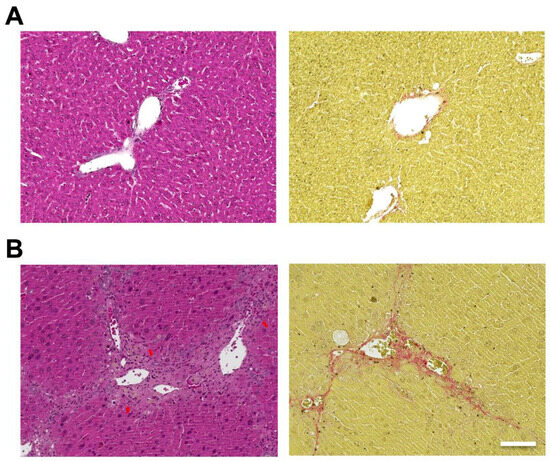

2.1. Evaluation of the Liver in Mice

5.2. Histological Analyses